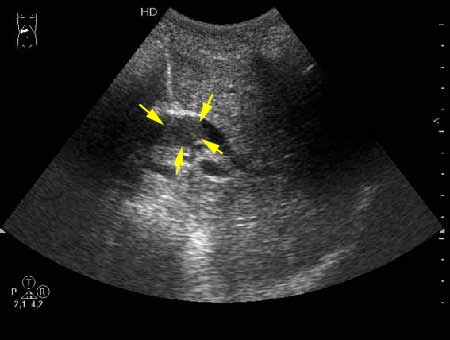

К сожаления, практически не видно. Если Вас не затруднит, пометьте стрелкой зону интереса.

А.М.Шифрин писал(а):К сожаления, практически не видно. Если Вас не затруднит, пометьте стрелкой зону интереса.

marked.jpg

Спасибо. Но даже по наводке визуализация очень нечеткая. Наверное, такие фото с очень "нежными" включаниями должны идти с максимальным качеством (а еще лучше видеоролик).

Гнойный холангит на фоне обструкции БДС конкрементом (камень вне скана). В холедохе определяется желчь с осадком, которая может быть ошибочно принята за его опухоль.